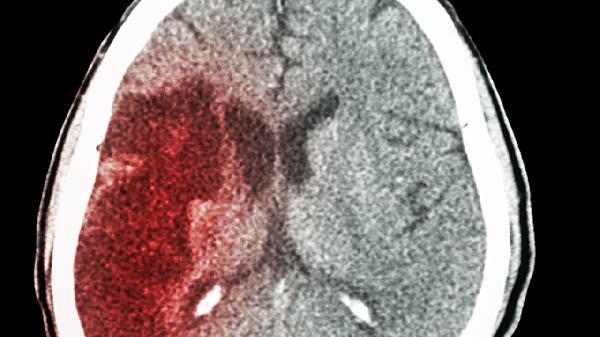

大多数接受车祸导致脑出血并进行开颅手术的患者,能够实现部分或完全的功能恢复。恢复的程度主要受到出血位置、手术时间、康复治...